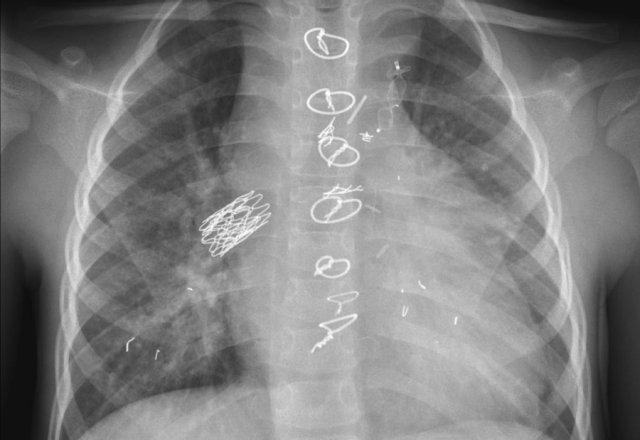

Các phát hiện bao gồm:

- Hai điện cực thượng tâm mạc kết nối với máy tạo nhịp

- ICD

- Hai điện cực đến mỏm thất phải

- Một điện cực chứa hai cuộn sốc điện

- Van ba lá (mũi tên)

- Van hai lá